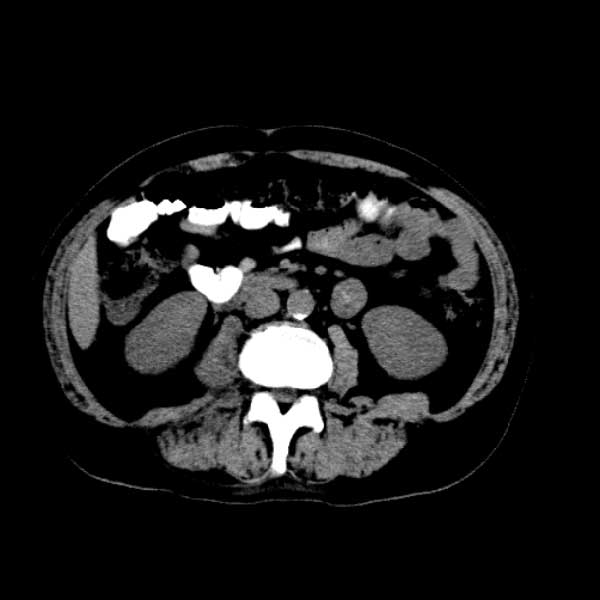

标题: CT13513:男 71 腹部疼痛20余天,近几天高热就诊,骨窗未见异 [打印本页]

标题: CT13513:男 71 腹部疼痛20余天,近几天高热就诊,骨窗未见异

考虑感染性病变可能性大,起源于阑尾?

感染,脓肿形成

考虑为化脓性阑尾炎.脓肿形成.及多肌肉累及.

考虑右侧腰大肌脓肿,向右髂窝、右腹股沟流注。

支持化脓性阑尾炎伴右髂窝脓肿、腰大肌腰方肌脓肿形成。

首先考虑化脓性阑尾炎伴腰大肌、腰方肌脓肿,不除外回盲部结核。

回盲部癌待排除。

患者肠镜检查考虑结肠癌,病理证实

患者肠镜检查考虑结肠癌,病理证实。肺部ct可见多发结节,考虑转移